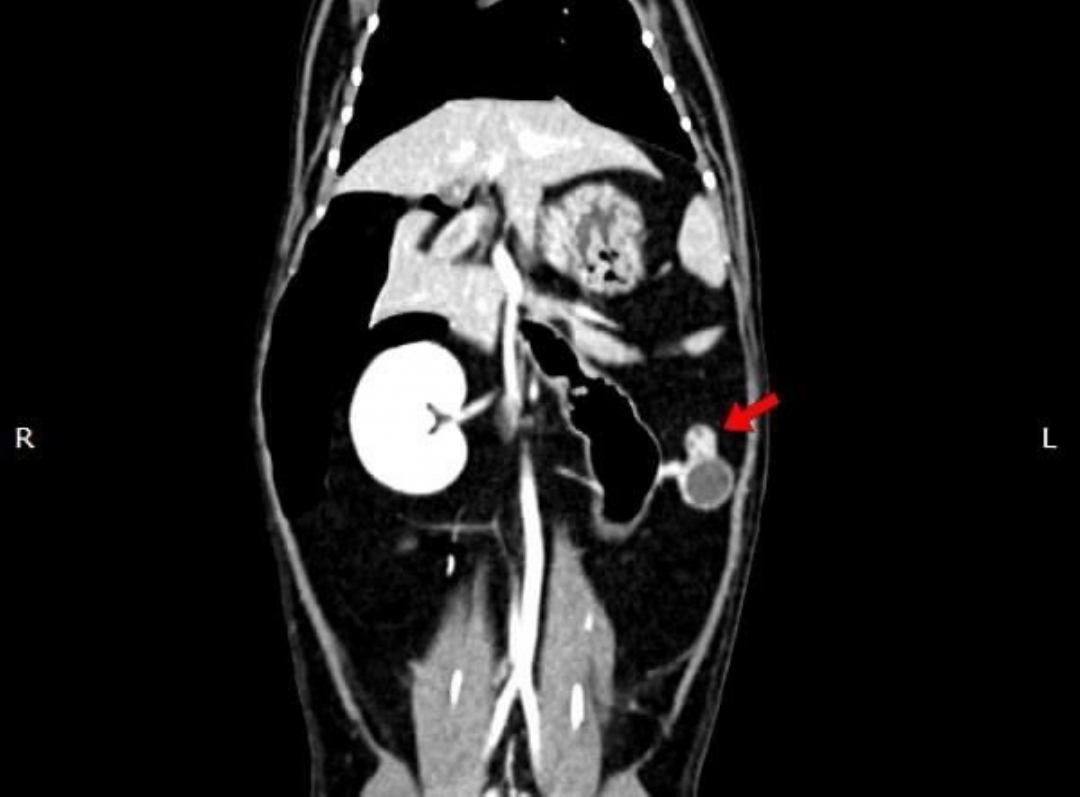

在他院絕育後仍有發情現象,轉院至築心,經由電腦斷層掃描確認後手術。